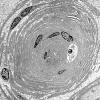

1K2 Massive Onion Bulbs (Case 1) EM 003 - Copy

1K3 Massive Onion Bulbs (Case 1) EM 009 - Copy

1K4AA Massive Onion Bulbs (Case 1) EM 025 - Copy